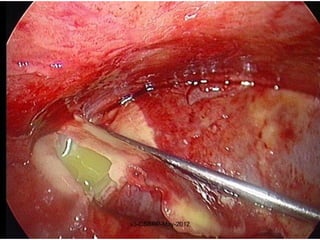

Ulcerative inflammation

FIGURE 2-21 The morphology of an ulcer. A, A chronic duodenal

ulcer. B, Low-power cross-section of a duodenal ulcer crater with an

acute inflammatory exudate in the base.

Gastric ulcer

Ulcerative inflammation FIGURE 2-21The morphology of an ulcer. A, A chronic duodenal ulcer. B, Low-power cross-section of a duodenal ulcer crater with an acute inflammatory exudate in the base. v3-CSBRP-May-2012